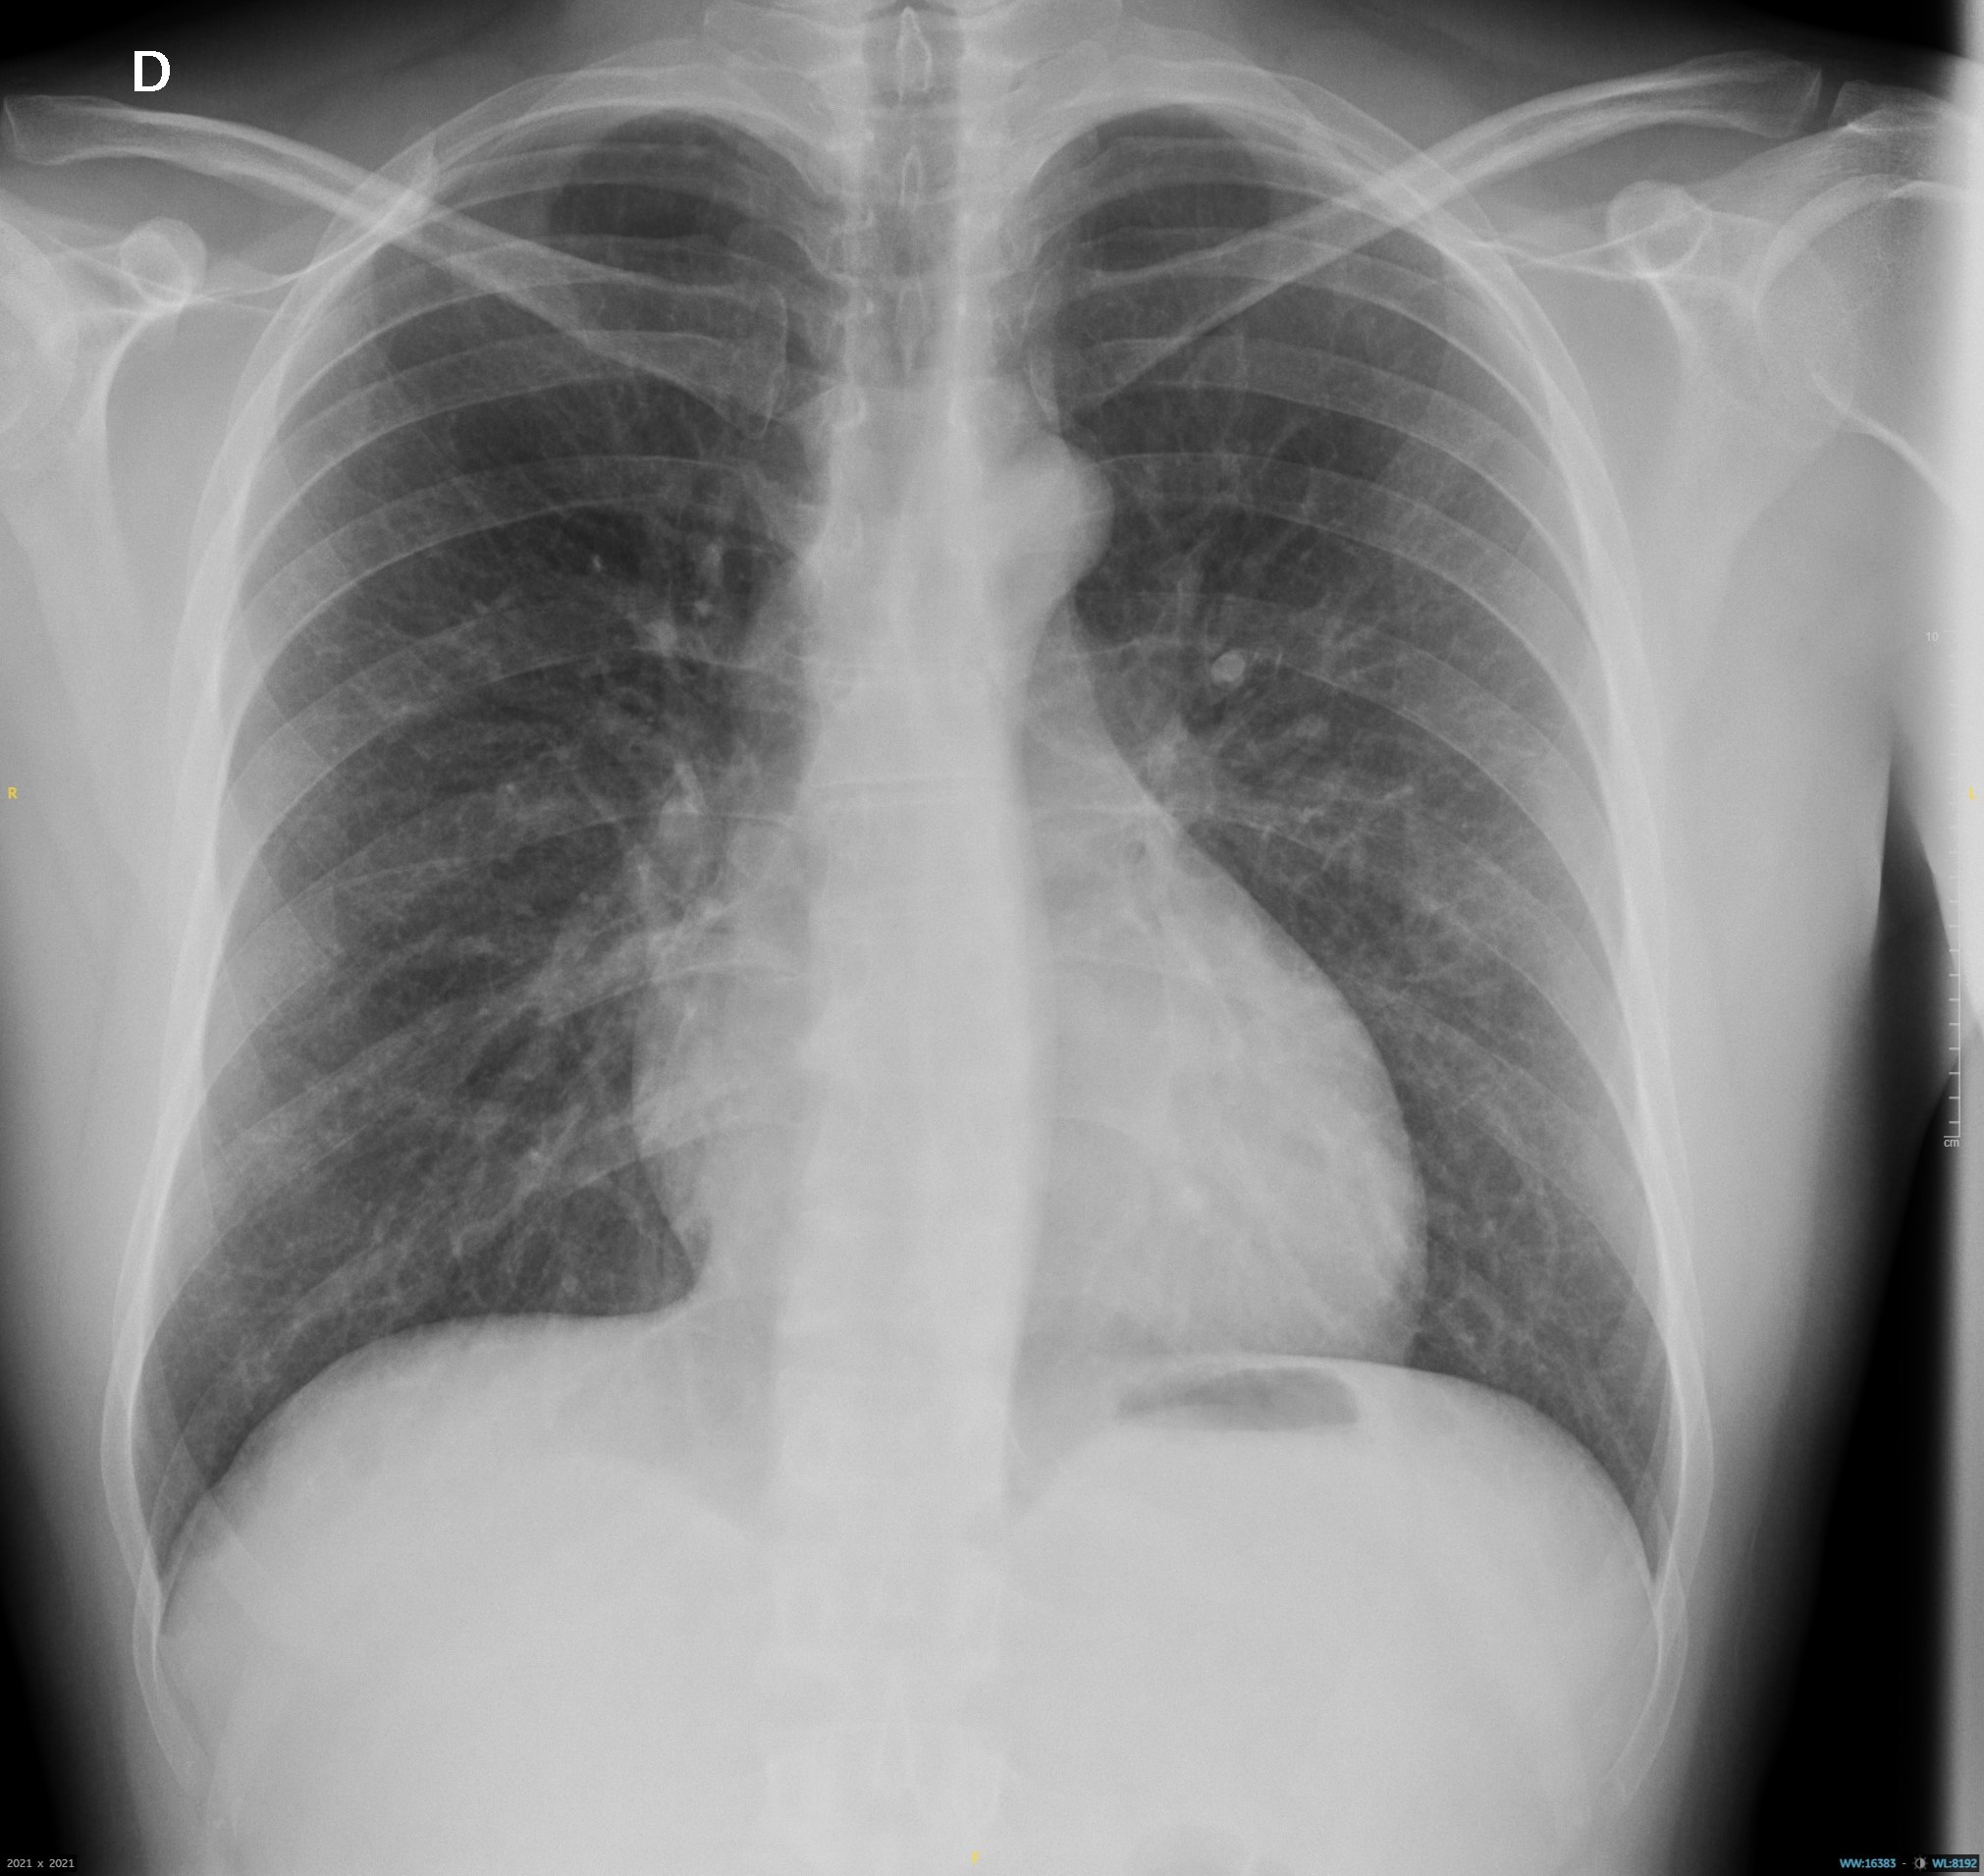

Plan de actuación: Se solicita analítica que incluye hemograma y perfil hepático, radiografía de tórax.

Evolución: Paciente con favorable evolución clínica, ausencia de progresión parasitaria con disminución de pápulas y pérdida de intensidad de la lesión eritematosa. En analítica se aprecia eosinofilia sin afectación hepática. Radiografía de tórax sin hallazgos patológicos.